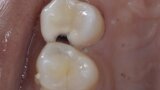

Predictable posterior restorations